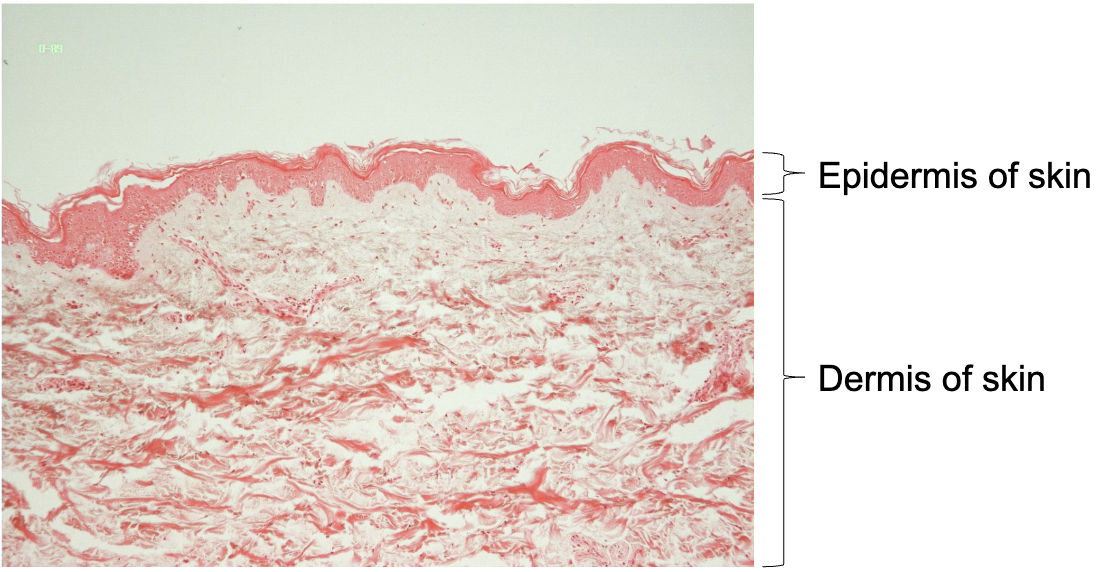

Label

Thin skin

Label strata of epidermis

Thin skin: Strata of epidermis